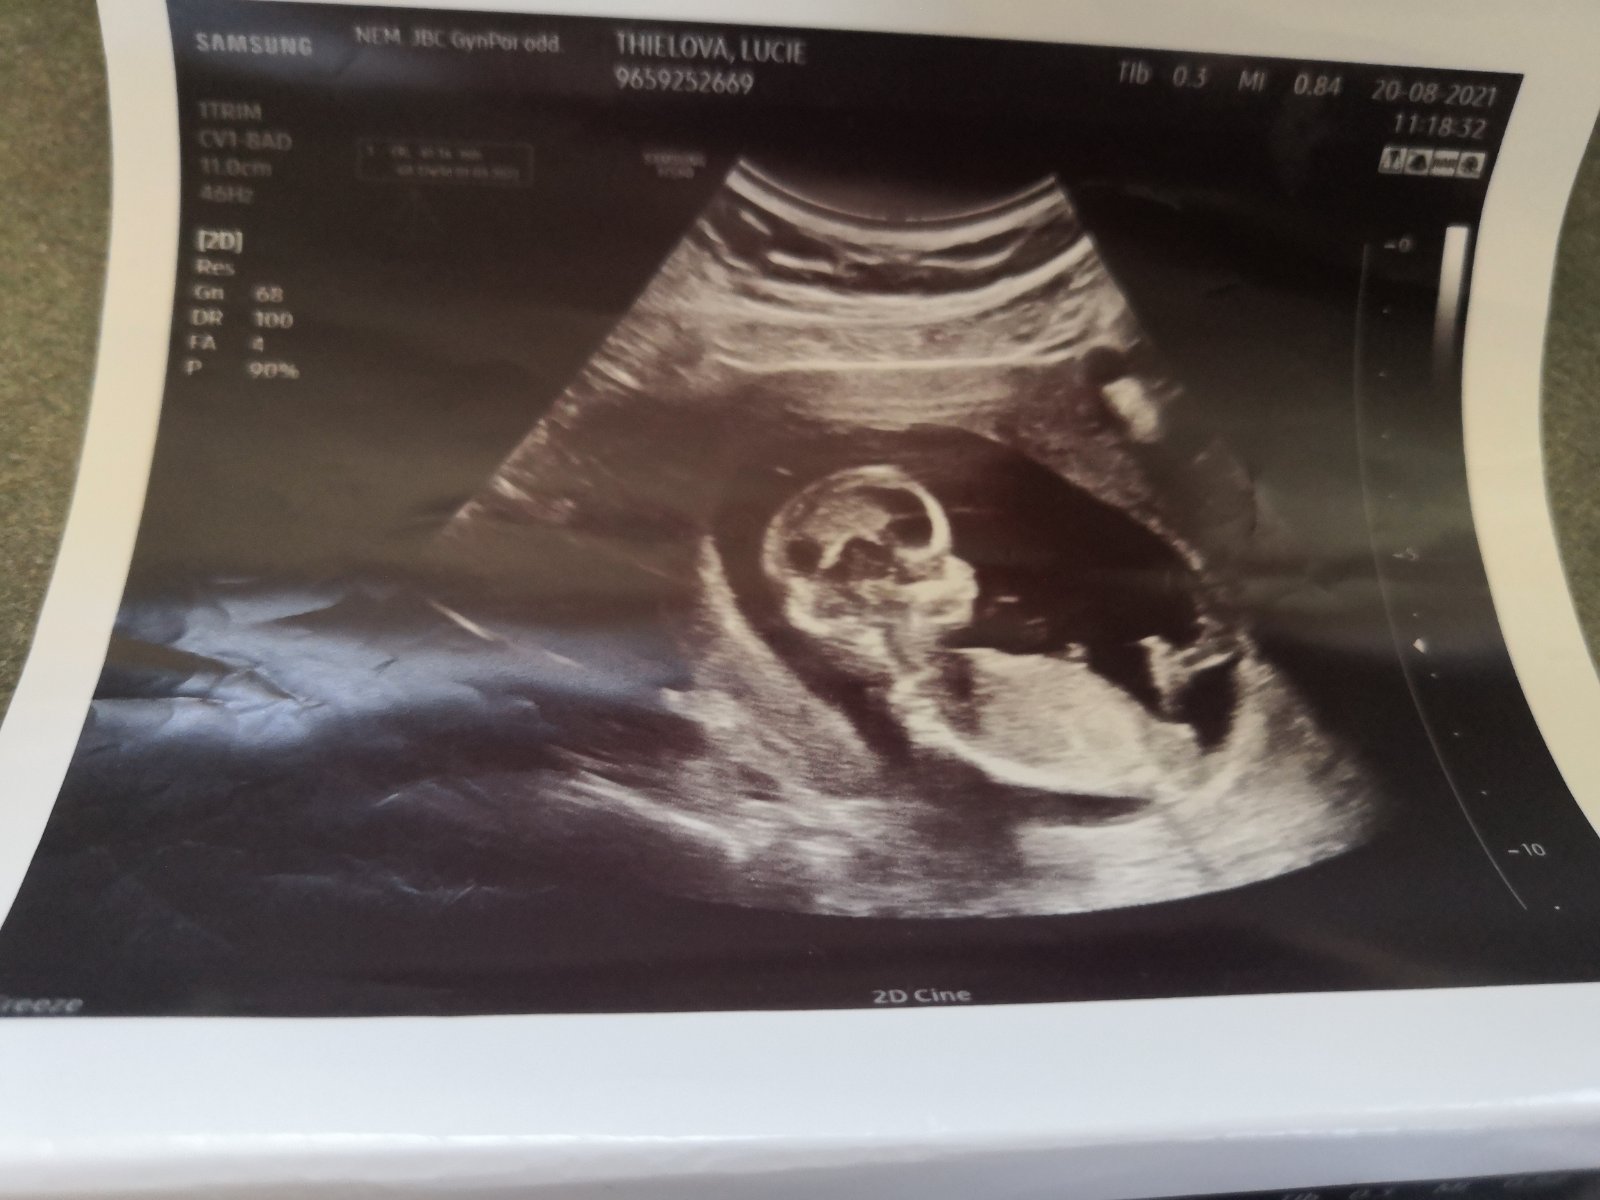

@luciethielova holka.

@luciethielova vypadá to na holčičku

Děkuji pěkně v holčičku doufáme máme doma jednoho chlapečka ale ať je to co je to hlavní je aby miminko bylo zdravé ❤️